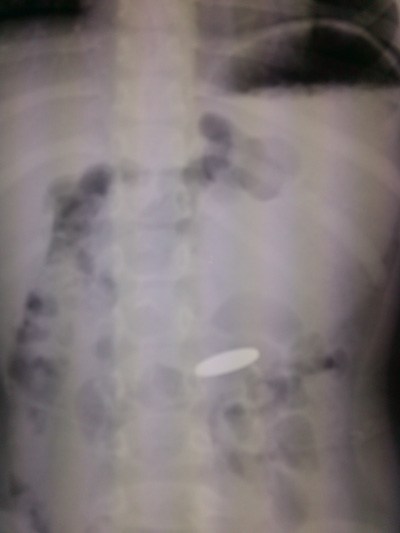

Ngày 19.12, Bệnh viện đa khoa Xuyên Á (TP.HCM) đã tiến hành ca phẫu thuật nội soi lấy ra đồng tiền xu từ dạ dày bé gái 4 tuổi.

Bác sĩ cho chụp X-quang kiểm tra và xác định đồng xu nằm trong dạ dày.

Đồng xu nằm trong dạ dày bé V., nhìn thấy qua X-quang - Ảnh: Bệnh viện cung cấp